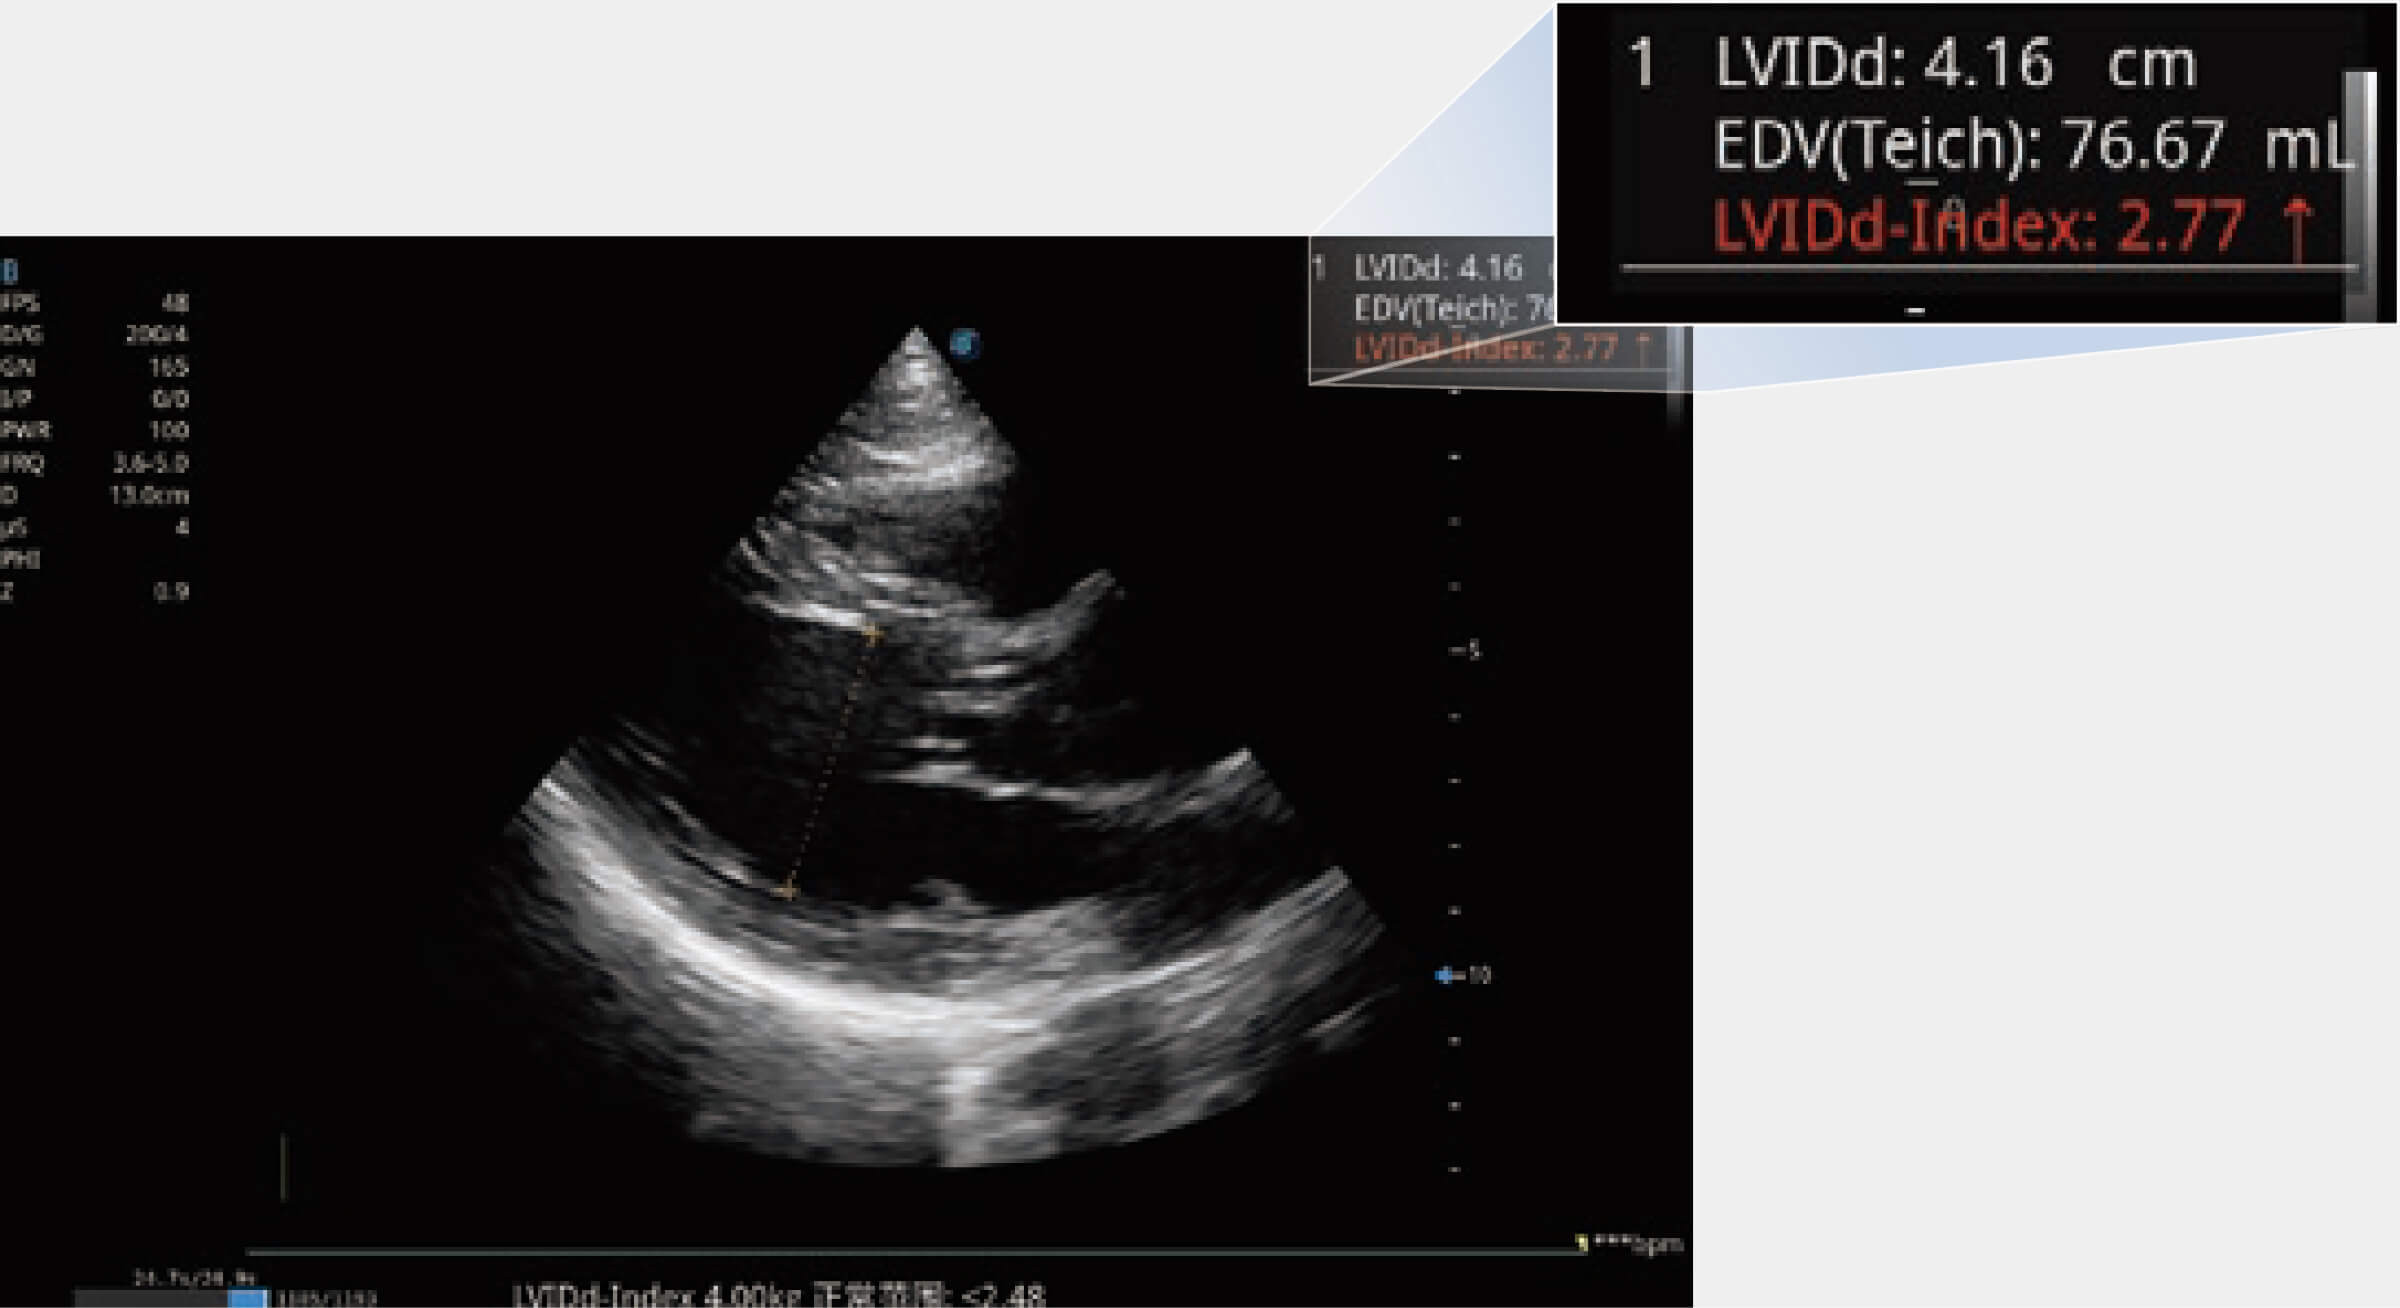

ProPet 80 專為動物醫(yī)生設(shè)計,對不同的動物體型和生理結(jié)構(gòu)作出了針對性的優(yōu)化。通過動物影像專用軟件,可滿足個性化的應(yīng)用需求,幫助動物醫(yī)生獲得更精確的診斷數(shù)據(jù)。

為精細(xì)結(jié)構(gòu)及組織邊緣提供高清晰度的圖像和更大的成像視野。幫助減輕醫(yī)生的用眼疲勞,快速精準(zhǔn)獲得測量的數(shù)據(jù)。

當(dāng)心臟測量結(jié)果超出正常范圍時,可實(shí)時預(yù)警提示動物醫(yī)生,減少疾病漏診概率。